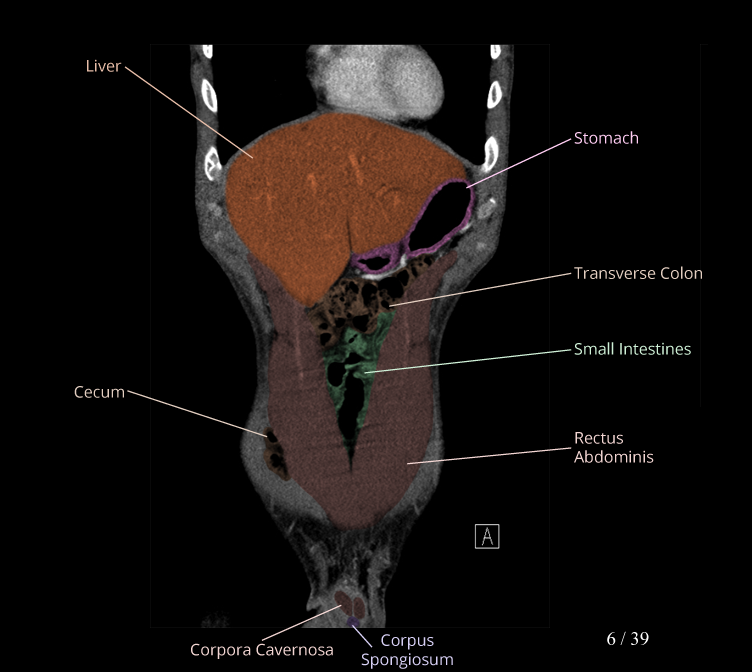

Body

Covers abdominal CT anatomy.